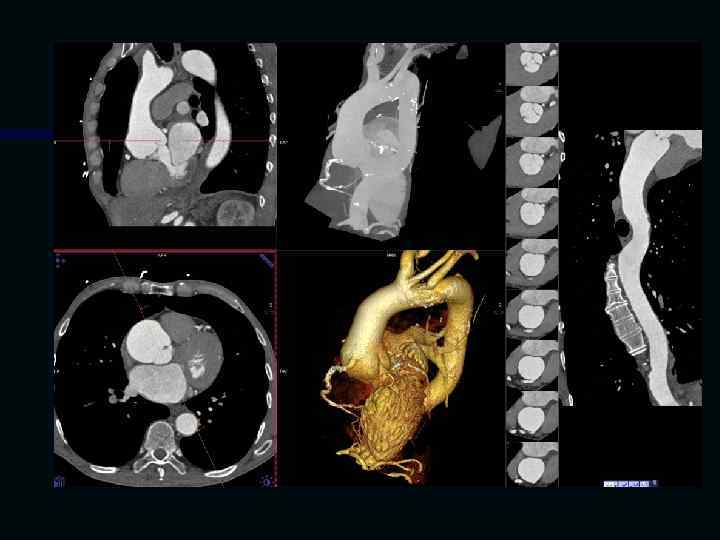

Исследование сосудов грудной клетки

Исследование сосудов брюшной полости